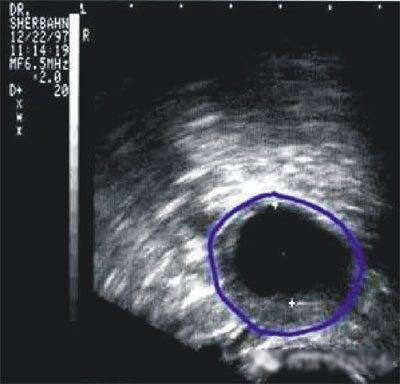

第三步:排卵監(jiān)測

常用的監(jiān)測排卵方法有基礎(chǔ)體溫測定(BBT)、陰道B超監(jiān)測排卵、血清性激素測定等。

(圖:排卵監(jiān)測)

陰道B型超聲動(dòng)態(tài)監(jiān)測卵泡的發(fā)育及排卵,是監(jiān)測排卵最準(zhǔn)確可靠的方法。通過陰道B超檢查可以了解子宮及雙側(cè)附件(卵巢和輸卵管)區(qū)的基本情況,測定卵巢內(nèi)的竇卵泡計(jì)數(shù),評估卵巢儲(chǔ)備功能,動(dòng)態(tài)監(jiān)測排卵。